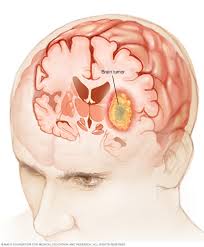

What Causes Brain Cancer In A Child / Brain Cancer Overview And More - Some kids who have certain genetic conditions have a greater chance of developing brain tumors.. These abnormalities are caused by alterations directly in the genes, or by chromosome rearrangements that change the function of a gene. And they vary between children. The majority of brain tumors have abnormalities of genes involved in cell cycle control, causing uncontrolled cell growth. As they get bigger, these tumors can press on the cells around them and cause damage. A brain tumor is a mass that grows in your child's brain, or in an area near the brain.

Astrocytomas are tumors that start in certain brain cells called astrocytes, which are a type of glial cell. This is different to cancers that have spread to the brain from somewhere else in the body. More children than ever are surviving childhood cancer. Childhood astrocytoma is a form of brain cancer in which cells in the brain start to grow abnormally. Astrocytoma is the most common type of glioma diagnosed in children. Learn about the causes, symptoms, and treatment of ependymomas, a type of spine and brain cancer that affects children and adults. Causes and risk factors for brain cancer the exact cause of brain cancer is unknown. Boys are affected slightly more often than girls. The majority of brain tumors have abnormalities of genes involved in cell cycle control, causing uncontrolled cell growth. A brain tumour is a collection of cells that have grown in an uncontrolled way. Although the drugs can be taken orally in pill form, in children with pediatric brain tumors the drugs are usually injected into a vein (intravenous chemotherapy). Examples include nerves in your child's skull, his pituitary gland, or the membranes that cover his brain. The cause of most childhood brain and spinal cord tumors is unknown.

Gliomas are tumors that form from glial cells and astrocytoma is a type of glioma. They can also indirectly damage cells by pushing on other parts of the brain. Neurofibromatosis, genetic disorder affecting nervous system von. Many chemotherapy drugs are available, and options depend on the type of cancer. Children with brain and spinal cord tumors have different needs from other children with cancer. Unlike cancer in adults, the vast majority of childhood cancers do not have a known cause. This is different to cancers that have spread to the brain from somewhere else in the body. Children with certain genetic conditions have an increased risk for tumors of the central nervous system. Which children are at risk for a brain tumor? In children, brain tumors may occur as a part of inherited syndromes like: Up to 10% of all cancers in children are caused by a heritable (germline) mutation (a mutation that can be passed from parents to their children). Alan cohen, m.d., director of pediatric neurosurgery at johns hopkins children's center, shares the most common signs and symptoms that could point to a potential brain tumor. The tumor may start in your child's brain or travel to his brain from another body area.

See your gp if your child has any symptoms of a brain tumour to get them checked over. Many children with a brain tumor experience headaches before their diagnosis. Most brain tumors in children start in the lower parts of the brain, such as the cerebellum or brain stem. When a child develops a brain tumor, early diagnosis is essential. Brain tumors can directly destroy brain cells.

Brain and spinal cord tumors are a common type of childhood cancer. Some kids who have certain genetic conditions have a greater chance of developing brain tumors. What is a brain tumor? Primary brain tumors involve a growth that starts in the brain, rather than spreading to the brain from another part of the body. Tumours that start in the brain are called primary brain tumours. The symptoms of childhood brain stem glioma vary and often depend on the child's age and where the tumor is located. Brain tumors are the most common solid tumors affecting children and adolescents, with close to 5,000 children diagnosed each year.; Brain tumors and other nervous system tumors make up about 27 percent of childhood cancers. Many tumors are more common at a certain age. The signs and symptoms of childhood brain and spinal cord tumors are not the same in every child. The tumor may start in your child's brain or travel to his brain from another body area. Examples include nerves in your child's skull, his pituitary gland, or the membranes that cover his brain. In general, brain tumors in children are very rare.